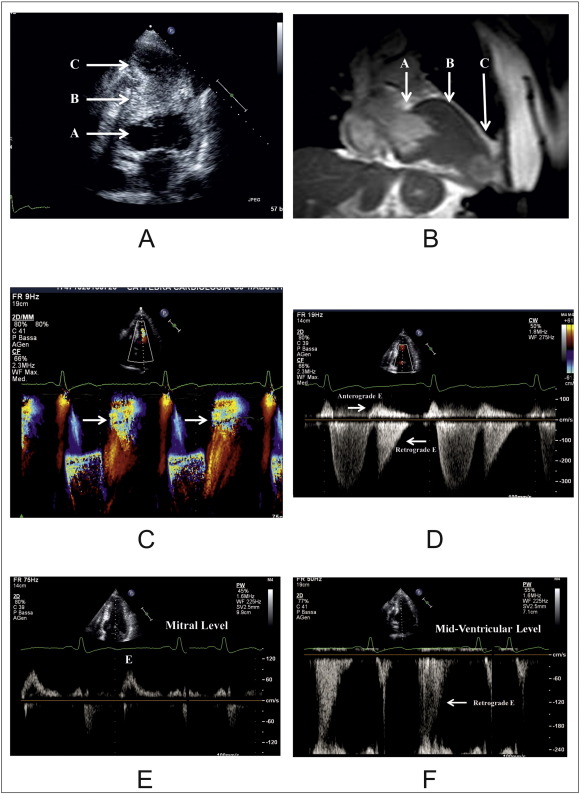

A patient with HCM, mid-cavity obliteration and apical aneurysm, diagnosed by both 2D echocardiography (Fig. 1, panel A) and cardiac magnetic resonance (Fig. 1, panel B), showed color Doppler aliasing effect at mid-ventricle toward the LV apex of early (E) diastolic velocity (Fig. 1, panel C). At continuous Doppler, E velocity resulted to be bidirectional (Fig. 1, panel D); pulsed Doppler identified the LV level at which E was highest (Fig. 1, panels E and F). The pullback pressure trace from LV apex to base, found a peak systolic gradient of 130 mm Hg, and a mean diastolic gradient of 10 mm Hg (Fig. 2). Such a gradient was of 15 mm Hg starting at early diastole and ending at meso-diastole, suggesting that apex fills during systole and empties during early diastole when the basal chamber has lower diastolic pressure.

A) Two dimensional 4 chamber view, showing the basal left ventricular chamber (A), the mid-cavity obliteration (B), and the LV apical chamber (C).

B) Cine balanced-fast field echo end-diastolic 2-chamber long-axis CMR view showing the basal left ventricular chamber (A), the mid-cavity obliteration (B), and the LV apical chamber (C).

C) M-Mode color Doppler echocardiography in the 4 chamber apical view. E velocity shows aliasing effect starting at mid-ventricle the apex (arrows).

D) Continuous Doppler in 4 camber view, showing that the early diastolic velocity is bidirectional within the left ventricle.

E) Peak E velocity at mitral leaflet tip level.

F) Peak E velocity at mid-ventricular level showing that at this level only retrograde high velocity E wave can be detected.